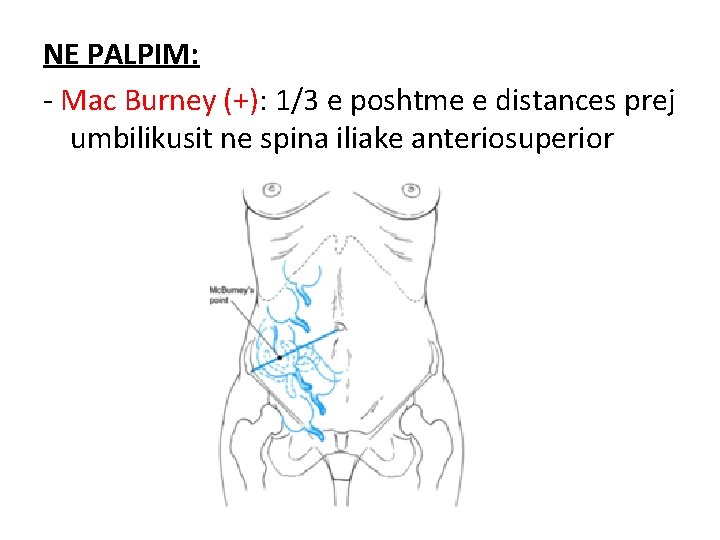

EKZAMINIMI FIZIK

NE PALPIM: - Mac Burney (+): 1/3 e poshtme e distances prej umbilikusit ne spina iliake anteriosuperior